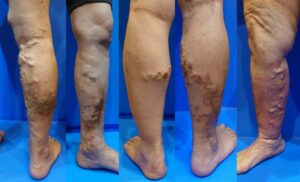

下肢静脉曲张

在早期阶段,很多患者只是发现腿部血管逐渐明显。

- 腿部血管凸起

- 血管弯曲像蚯蚓一样

- 血管越来越明显

- 皮肤色素沉着(皮肤变黑)

- 湿疹

- 皮肤炎症